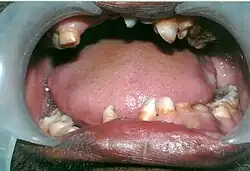

Facial and forehead changes along with increased mobility of the shoulder girdles

Cleidocranial dysostosis (CCD), also called cleidocranial dysplasia, is a birth defect that mostly affects the bones and teeth.[1] The collarbones are typically either poorly developed or absent, which allows the shoulders to be brought close together.[1] The front of the skull often does not close until later, and those affected are often shorter than average.[1] Other symptoms may include a prominent forehead, wide set eyes, abnormal teeth, and a flat nose.[1] Symptoms vary among people; however, intelligence is typically unaffected.[1]

• The permanent teeth include supernumerary teeth. Unless these supernumeraries are removed they will crowd the adult teeth in what already may be an underdeveloped jaw. If so, the supernumeraries will probably need to be removed to make space for the adult teeth. Up to 13 supernumerary teeth have been observed. Teeth may also be displaced. Cementum formation may be deficient.[13]

• Failure of eruption of permanent teeth.